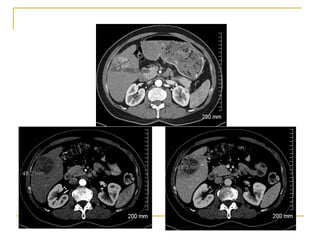

Recurrence rates with RFA appear lower than PEI at the expense of higher complications and cost

Complete response in 80% of tumors less than 3 cm and 50% if 3-5 cm

Best results – 5 year survival of 40-70%

Predictors of best results– Child-Pugh A, single tumors, less than 2 cm, initial response

Current Role of RFA

Indications

Primary treatment instead of partial hepetectomy for lesions < 3 cm

Unresectable small HCC

Recurrent small HCC

Bridging therapy before liver transplantation

Increasing role in 3-5 cm lesions